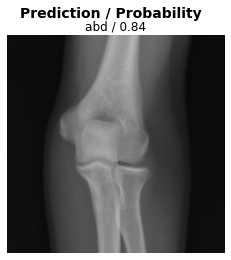

Test the model on a surprise example

Here, we present the model with an unexpected image (an elbow radiograph) and see how it responds.

fig.suptitle('Prediction / Probability', fontsize=14, fontweight='bold')

x_dec.show(ctx=ax)

ax.set_title(f'{dls.vocab[res[2][0]]} / {max(res[0][0]):.2f}');

When presented with this radiograph of an elbow, the model makes a prediction but is less confident than with the other test images.

Important: (1) A deep learning classification model can only learn what we teach it to learn.

Important: (2) In designing our model implementation, we might consider designing a pre-processing step in which the data (or metadata) is checked to ensure the input to the model is valid.